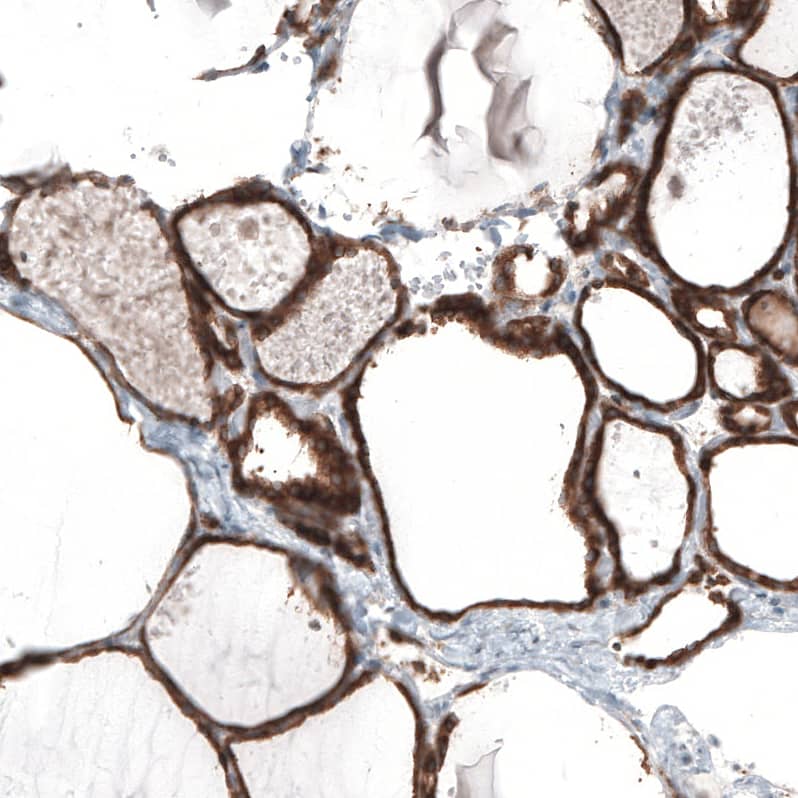

Staining of human thyroid gland shows strong positivity in cytoplasm granular in glandular cells.